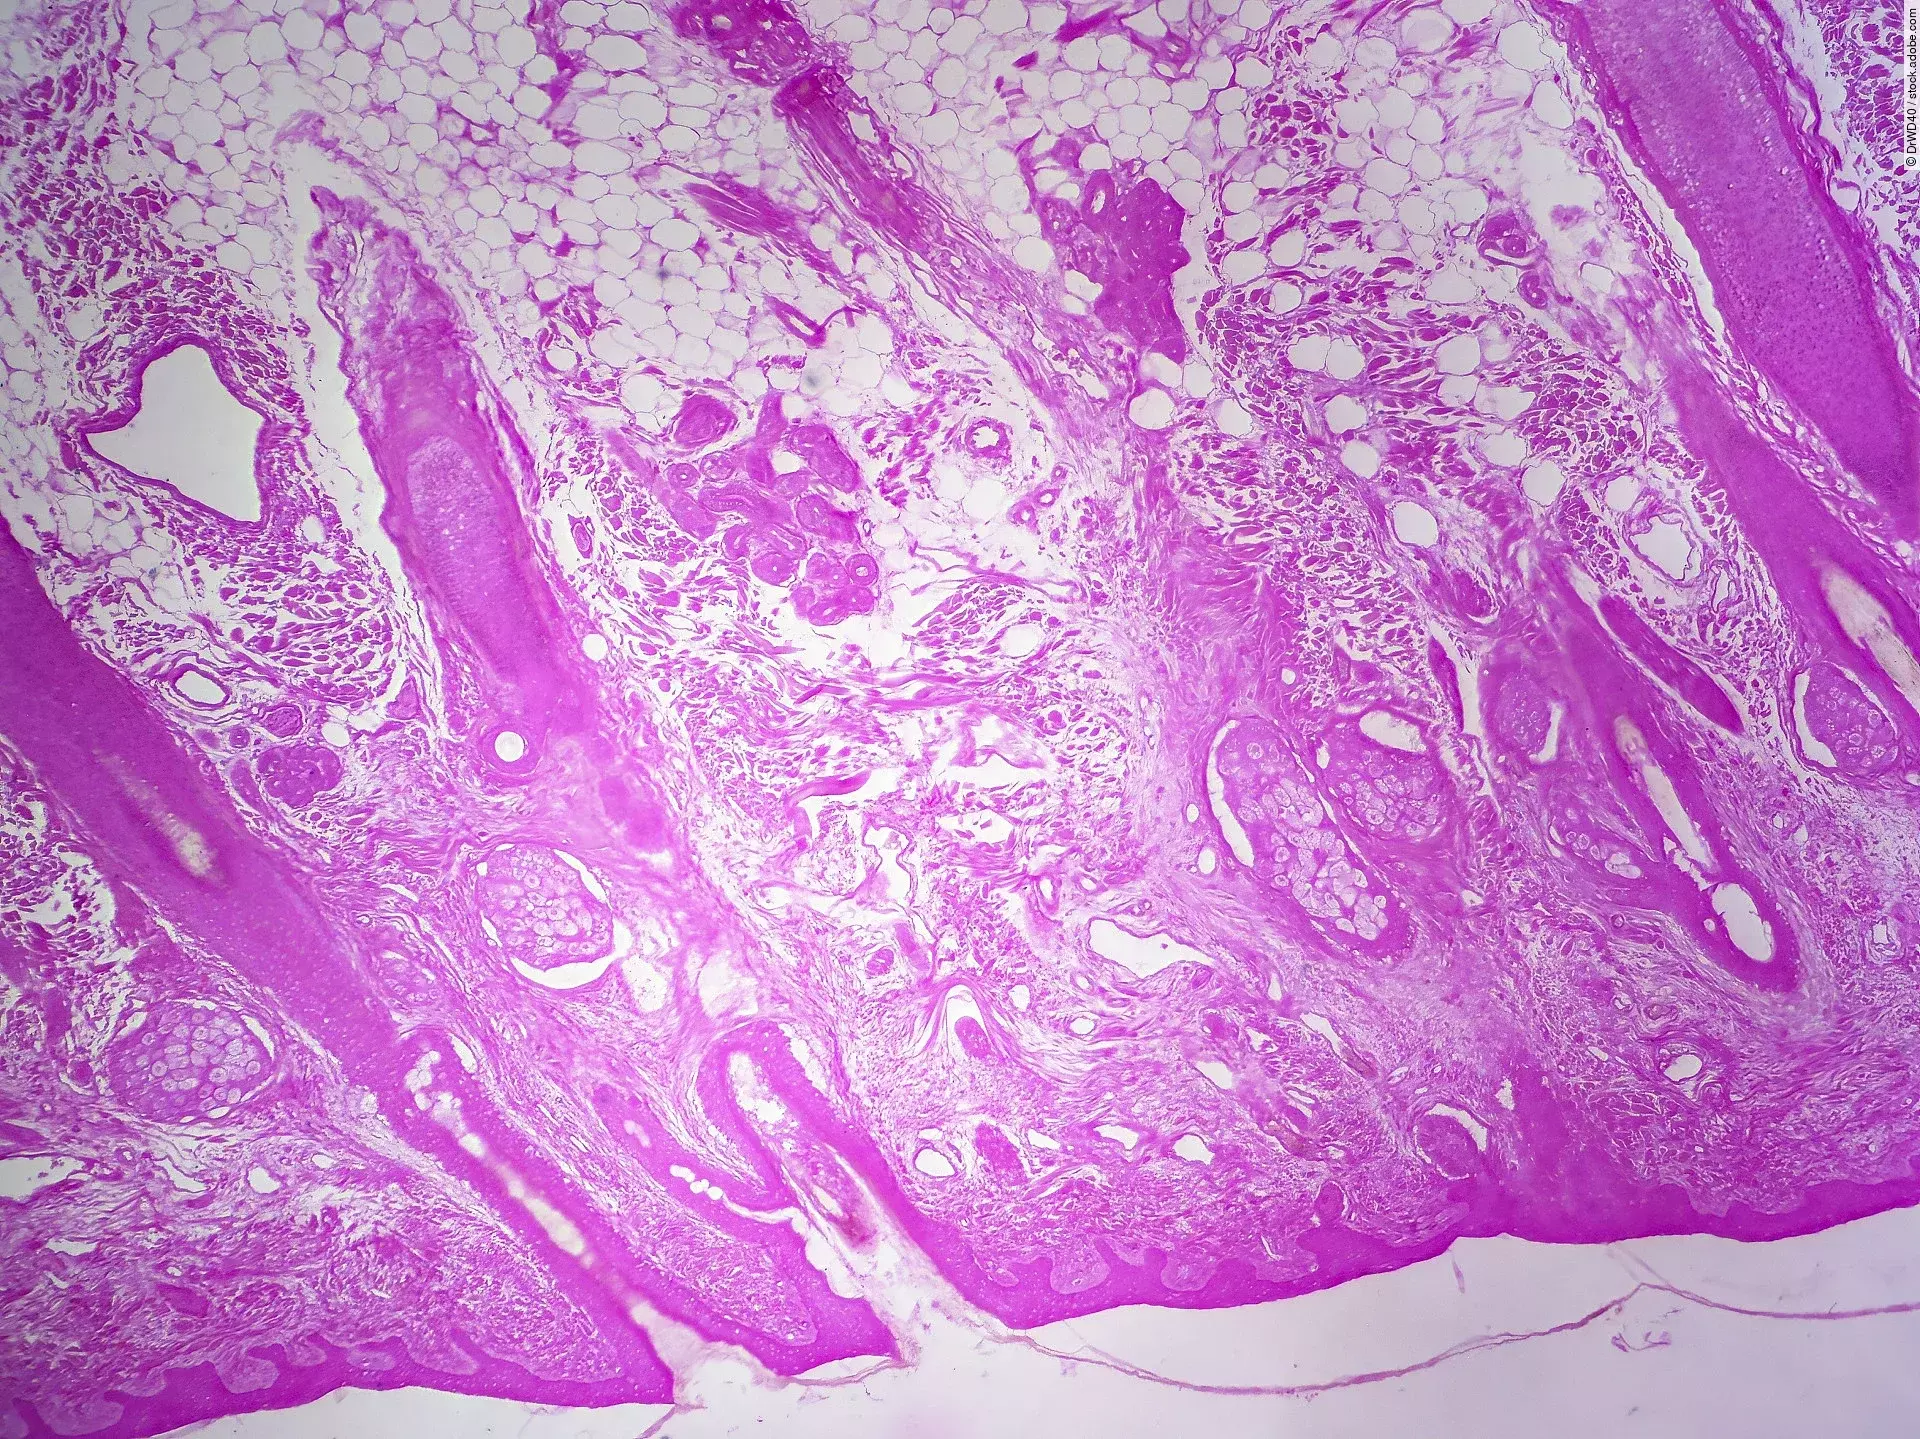

Forschenden des Frauenhofer-Instituts ist es gelungen, eine reproduzierbare In-vitro-Hundehaut im Labor herzustellen. Verträglichkeits- und Wirkungstests können nun ganz ohne Tierversuche durchgeführt werden.